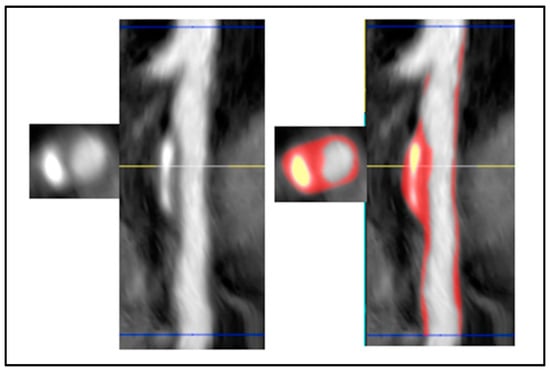

6. Cardiac Magnetic Resonance Imaging

- Lanzafame, L.R.M.; Bucolo, G.M.; Muscogiuri, G.; Sironi, S.; Gaeta, M.; Ascenti, G.; Booz, C.; Vogl, T.J.; Blandino, A.; Mazziotti, S.; et al. Artificial Intelligence in Cardiovascular CT and MR Imaging. Life 2023, 13, 507. [Google Scholar] [CrossRef] [PubMed]